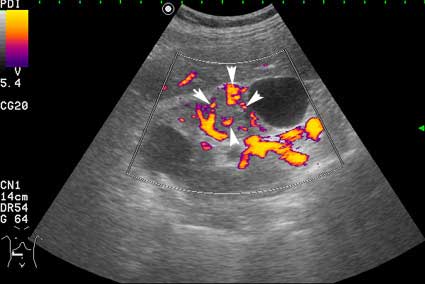

Сканирование в режиме энергетического доплера.

Вас не смущает наличие внутреннего кровотока в одной из "кист"?

При гистологии эта структура была почечно-клеточным раком (RCC).

Согласен, но есть совокупность признаков, позволяющих с очень высокой степенью достоверности считать, что это тканевое образование, а в отношении конкретного случая - что это почечноклеточный рак (RCC).

Но Вы правы в том, что могут быть трудности в дифференциальном диагнозе между AML и RCC малых размеров (в 20-30 % случаев могут быть эхогенными). Однако при УЗИ для RCC характерен гипоэхогенный ободок, внутриопухолевые включения, низкорезистивный внутриопухолевый кровоток.